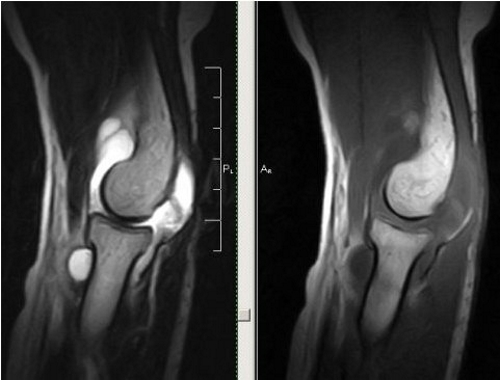

Онкологические заболевания локтевых суставов встречаются редко, и опухоли чаще всего доброкачественные. Диагностика с использованием томографии рекомендуется при обнаружении воспалительного процесса в мягких тканях. Костные опухоли сложно выявить на рентгеновских снимках, однако МРТ с контрастом позволяет получить четкую картину заболевания.

Томография позволяет качественно оценить происхождение различных болей, возникающих при спортивных травмах. Двухмерные снимки с послойным изображением мягких тканей и хрящей помогают точно определить место травмы и характер повреждения.

Томография — это эффективный метод исследования локтевого сустава. МРТ предоставляет четкое изображение суставных поверхностей и хрящей, а также позволяет детально рассмотреть связки, сухожилия, мягкие ткани, кровеносные сосуды и нервные окончания. На основе выявленных отклонений от нормы специалист может установить следующие диагнозы:

Иногда с помощью томографии трудно установить причину опухолей мягких тканей. Тем не менее, некоторые из них можно визуализировать и охарактеризовать, например, доброкачественную липому и сосудистую гемангиому. МРТ для выявления патологии рекомендуется проводить до биопсии, чтобы избежать искажений анатомической картины из-за возможных кровоизлияний, воспалений и отеков, вызванных удалением ткани.